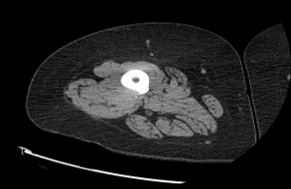

Muscle at ICU admission (light grey)

Same muscle 6 months post-ICU discharge

Patients ventilated and sedated in the ICU are most at risk of developing ICU-acquired weakness. Muscle loss can progress as quickly as 2-4% per day. 50% of patients 65 or older, on a ventilator in the ICU for a week or more experience permanent disability.